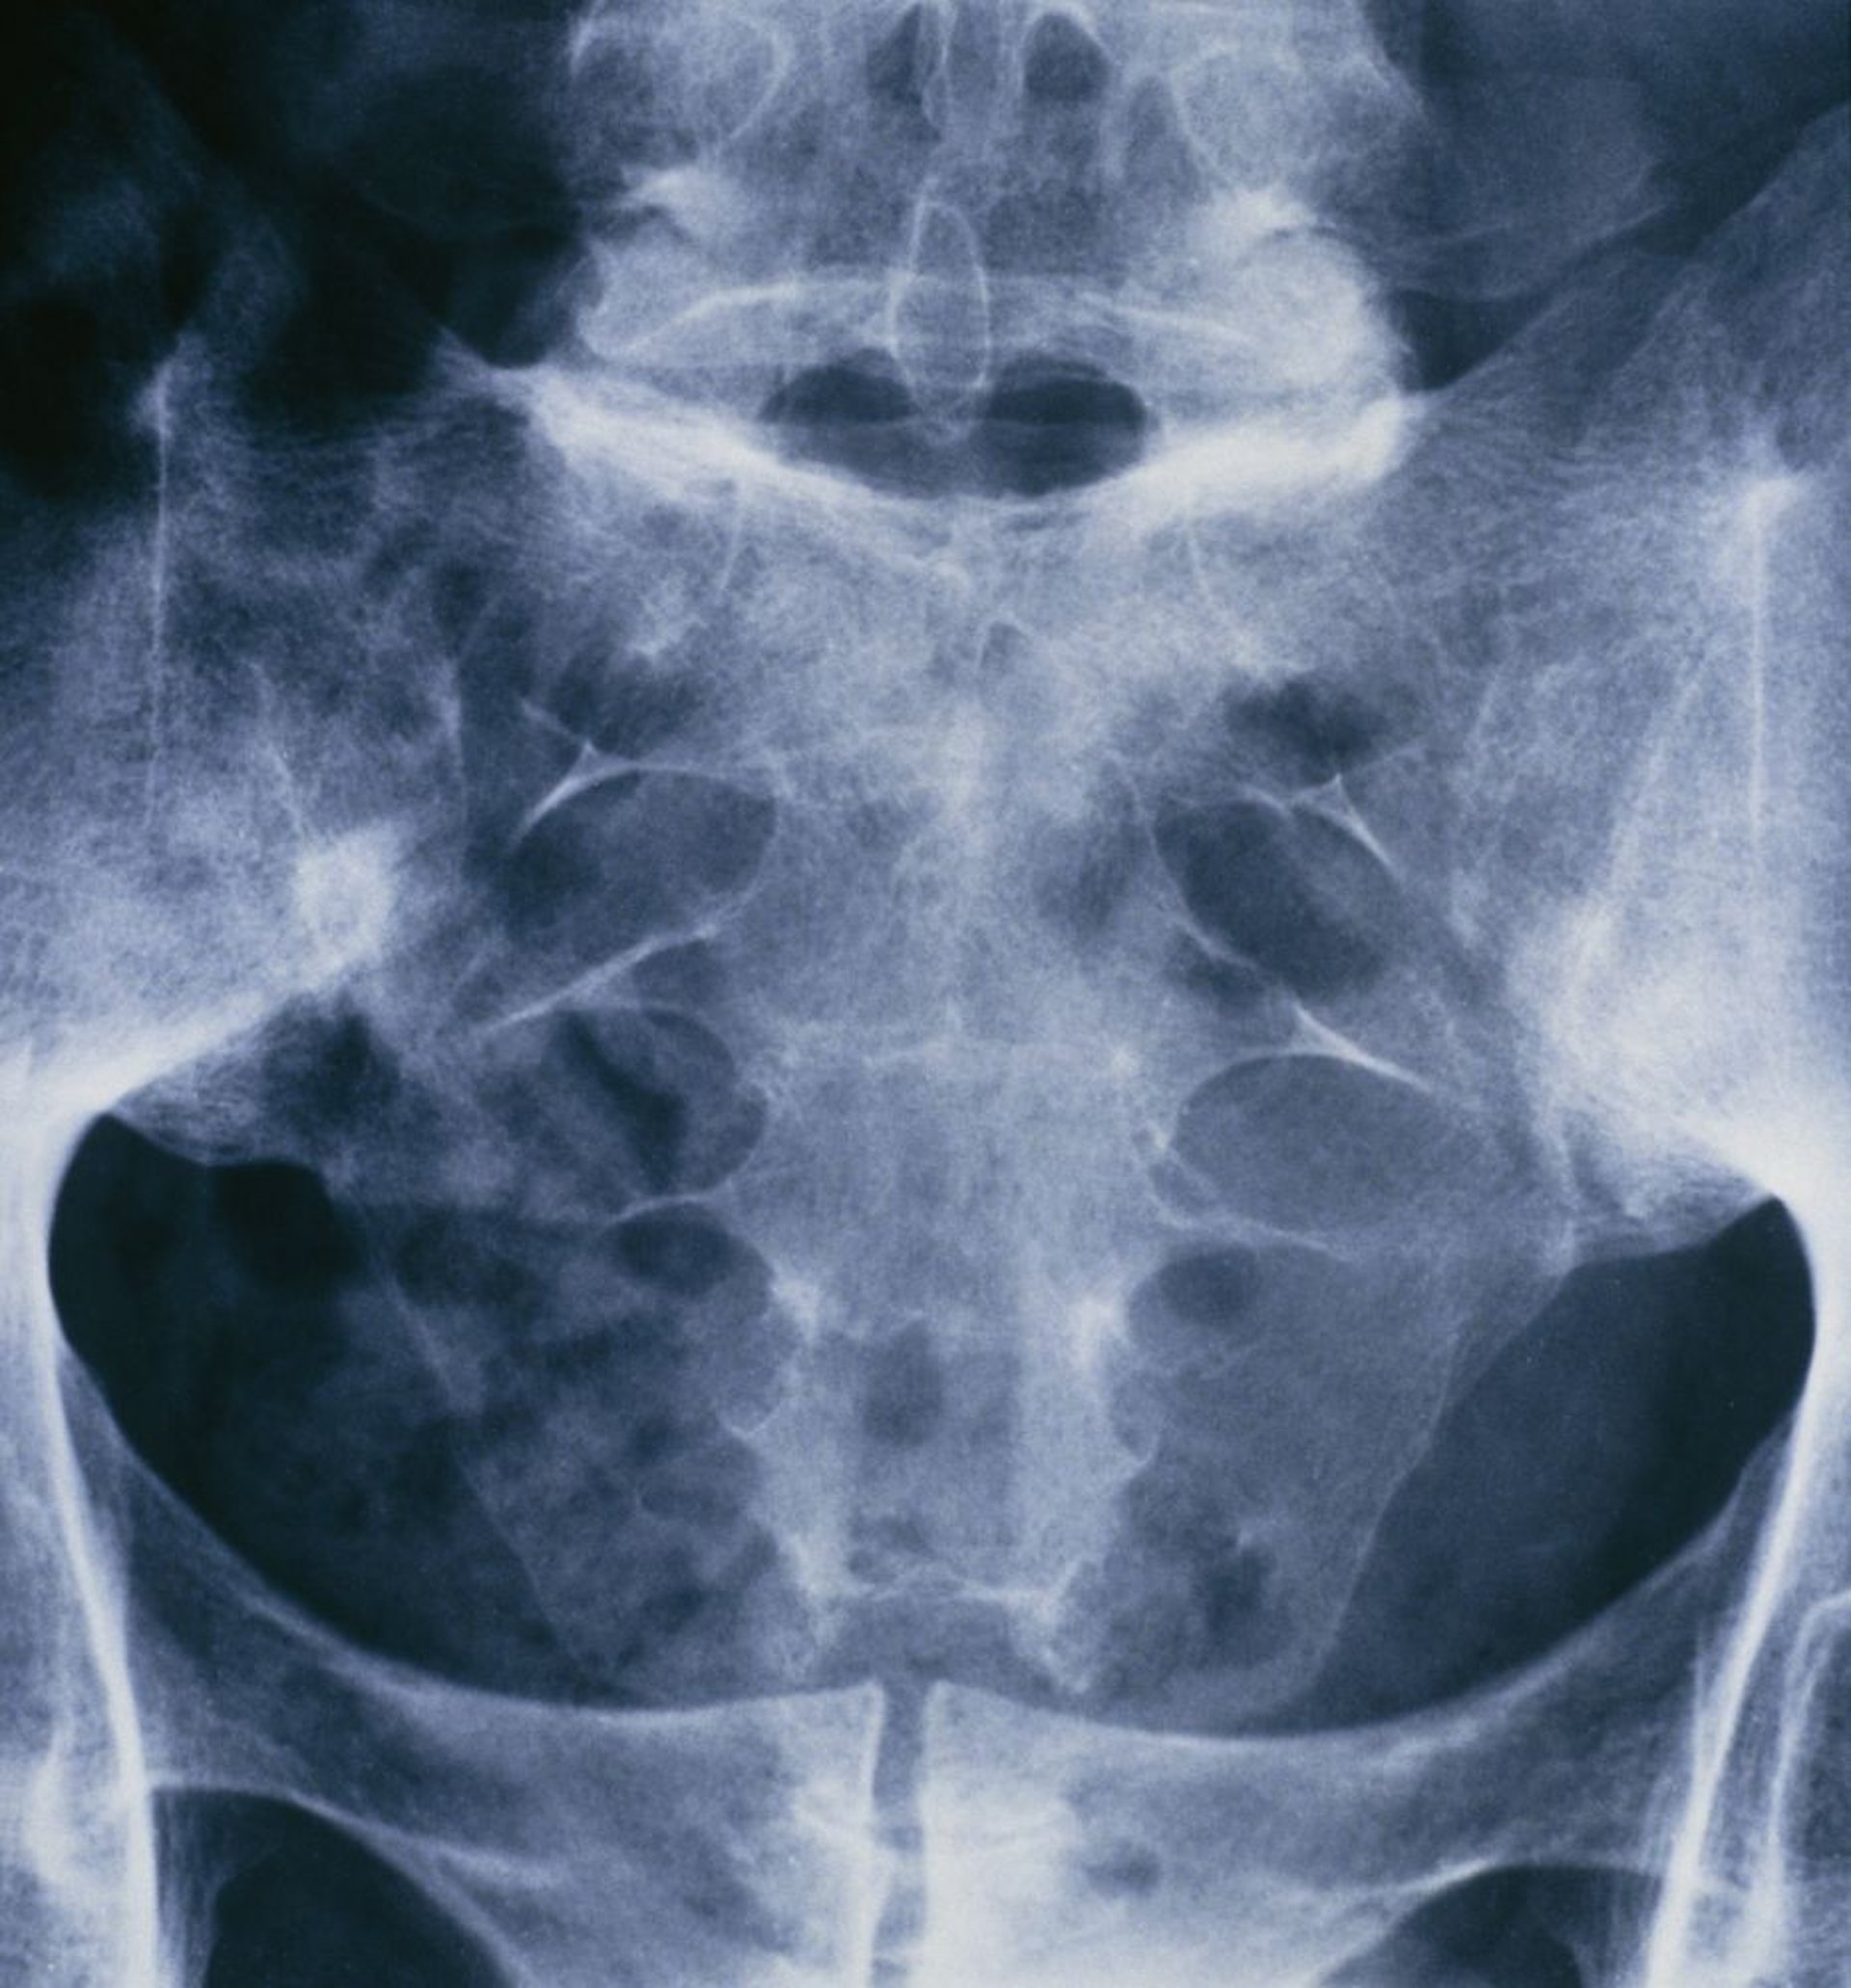

Ankylosierende Spondylitis (Sakroilitis)

Diese Röntgenaufnahme des Beckens und der sakralen Wirbelsäule einer an Morbus Bechterew erkrankten Person zeigt eine Verschmelzung beider Iliosakralgelenke.

ST. BARTHOLOMEW'S HOSPITAL, LONDON/SCIENCE PHOTO LIBRARY